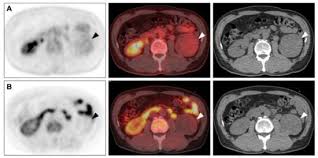

The F-Conal FDG PET scan uses a radiotracer called F-18 Fluorodeoxyglucose (FDG), which highlights areas of abnormal metabolic activity in the body. Since cancer cells absorb more glucose than normal cells, this scan is extremely effective in identifying tumors and monitoring treatment.

High-resolution imaging

Precise tumor localization

Early detection of abnormalities